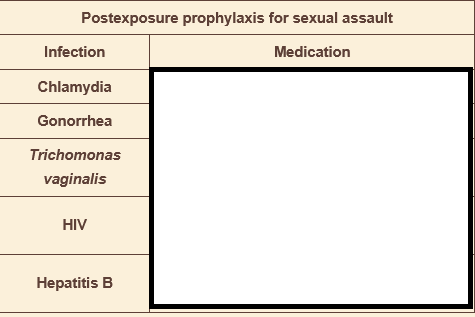

decreased fetal movement & nonpainful but regular contractions, no prenatal care. mother has fatigue, joint stiffness, and erythematous, confluent facial rash

fetal AV block due to mother’s lupus